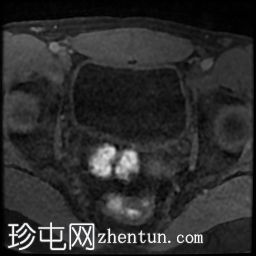

轴位

DWI

前列腺大小为32.8 x 41.5 x 34.7 mm(前后径 x 宽度 x 头尾径),体积为25.88 ml,属于正常范围。前列腺中央可见一逗号状囊性占位性病变,大小为17.3 x 12.1 x 9.3 mm(头尾径 x 前后径 x 宽度)。可见囊肿与前列腺尿道相通。囊内未见可疑内容物——具体而言,未见囊内出血或碎屑——弥散加权成像结果为阴性,提示无囊内感染。

本例为一例发生于青年人的单纯性逗号状中央型前列腺内囊肿。

根据囊肿位于前列腺中央或中线(精阜水平)、患者年龄(二十岁左右)以及无前列腺外延伸和明显的尿道交通,前列腺囊肿是首选诊断。苗勒氏管囊肿通常难以排除。患者的年龄、无前列腺外延伸以及疑似尿道交通使该诊断的可能性降低。